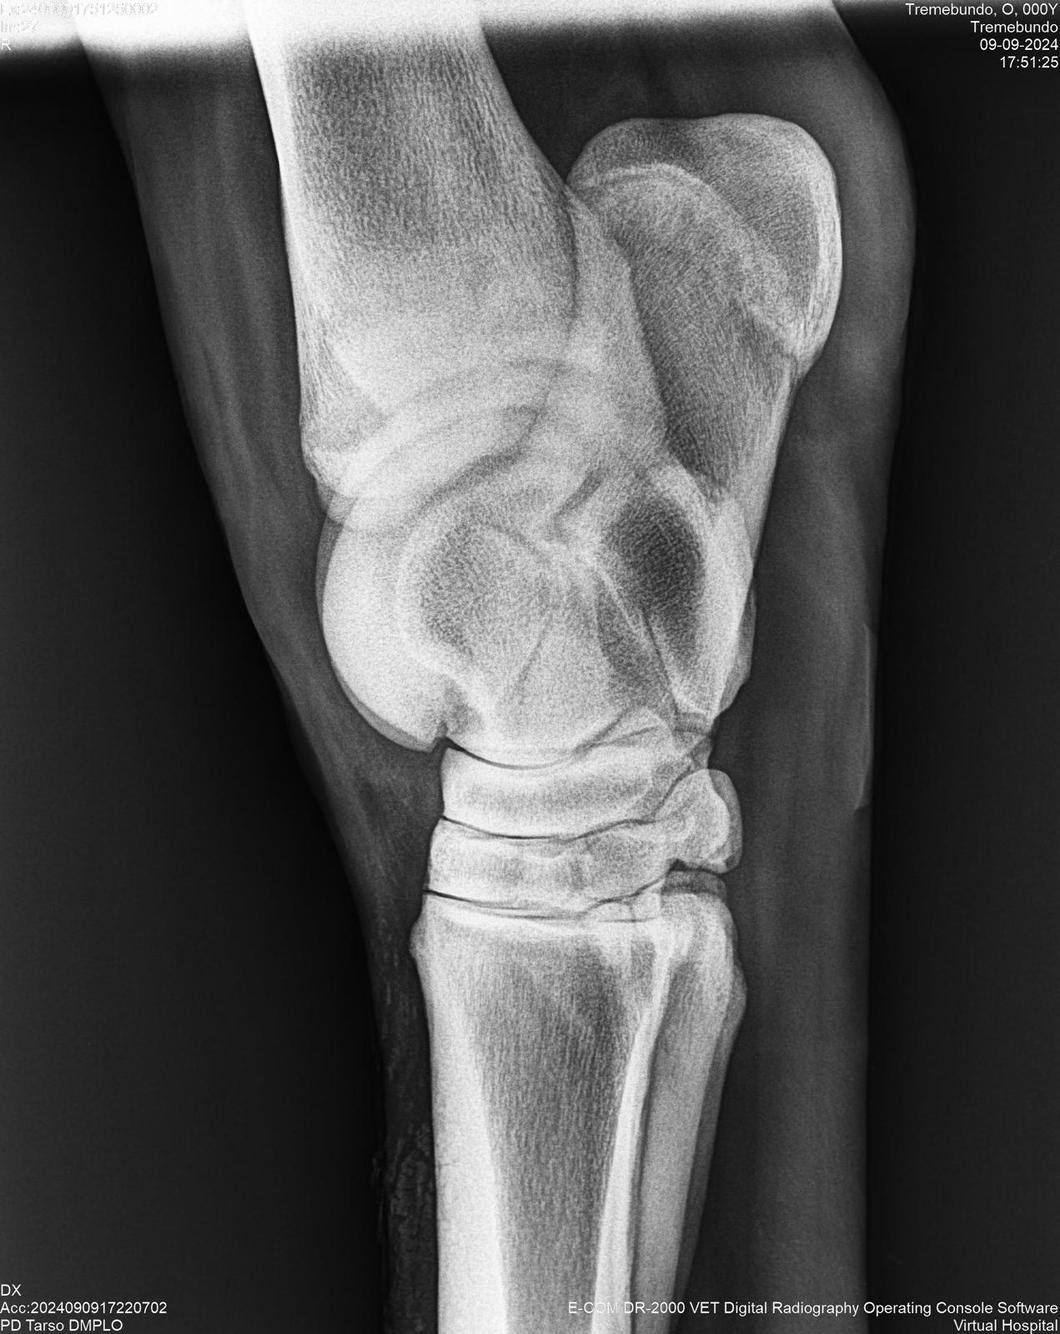

LOTE 37, TREMEBUNDO

Identificador: #291140-

Generacion 2022